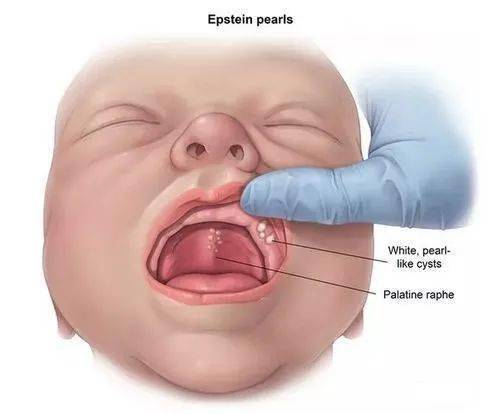

一,鹅口疮

图片尺寸500x370

这雪白却是一道忧心风景,小儿鹅口疮护理要有方

图片尺寸400x576